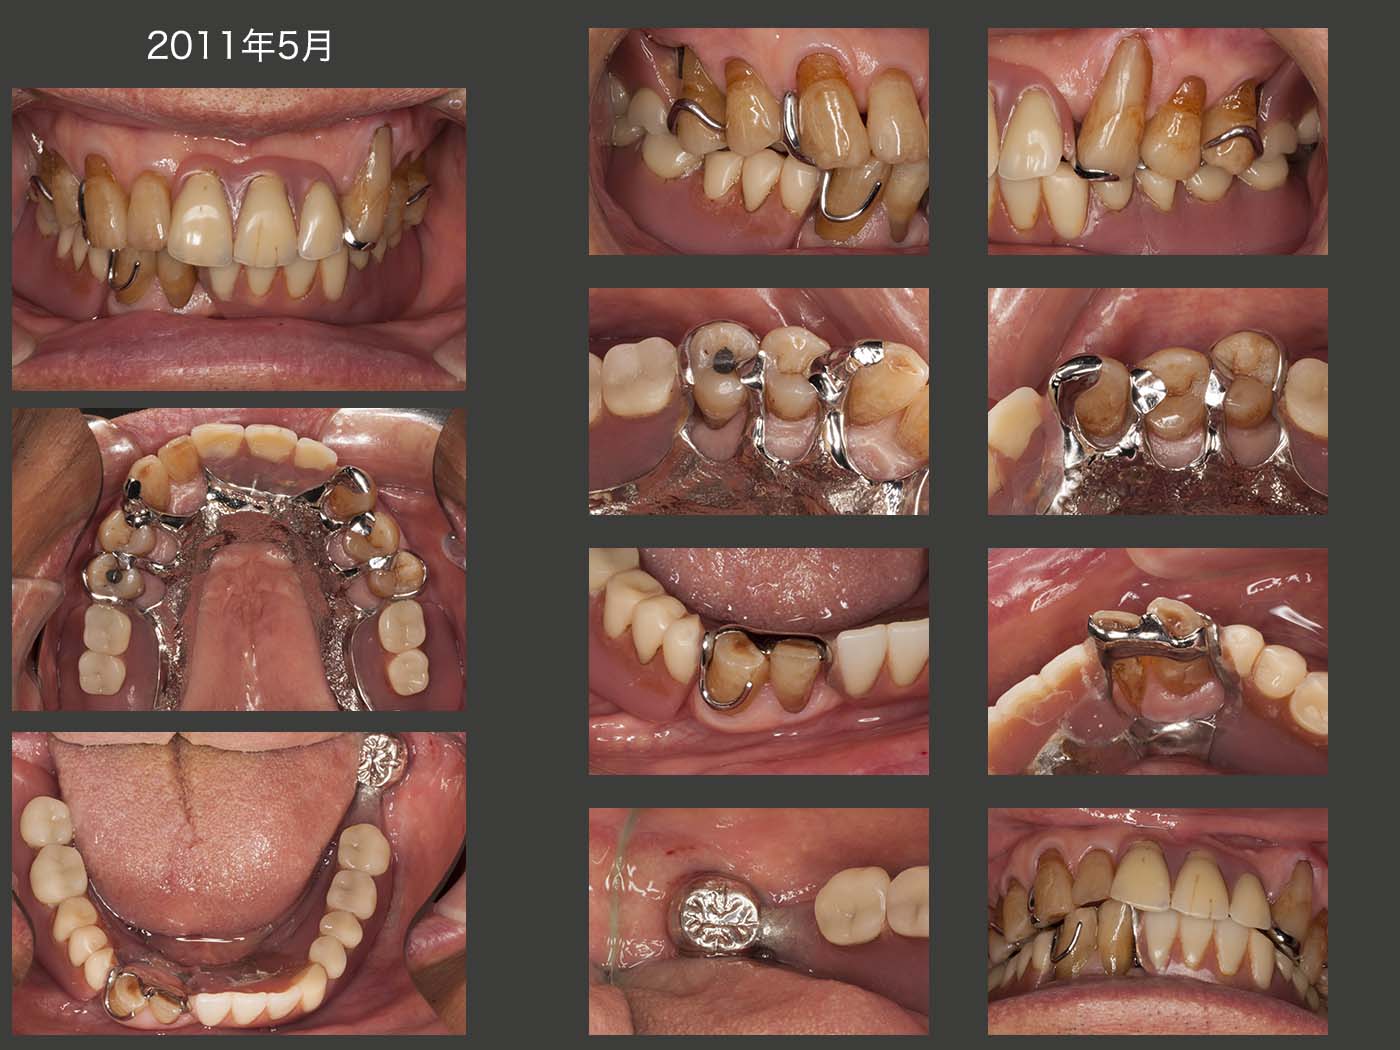

2021年1月,初診終了後31年7ヵ月の状態.上段左に示す1995年8月のデンタルX線写真と比べて,25年5ヵ月後となる上段右に示す21年1月の状態は,左下1,2が失われ,右上5が根面カリエスから抜髄(00年4月)された以外はほとんど変化がみられなかった.特に,歯周ポケットに変化がみられなかったことから,歯の清掃性はまずまずであり,患者さんが力をあまり加えないで上手に咀嚼できたことが功を奏したのではないかと推察する.なお今回,左上の4,5の根面カリエスにコンポジットレジン充塡を行った.

2021年1月,初診終了後31年7ヵ月の義歯装着時の状態.下顎の義歯においては,2〜3年に1回の割合で,義歯が破折し,その度に修理およびリライニングを行っている.一般的に支台歯が片側に偏った症例は,義歯の維持安定を得るのが難しい.しかし,たまに修理およびリライニングを行う以外,咀嚼にそれ程不満を訴えなかったことは,左下8の存在が大きいと思われる.(上下顎に犬歯が4本残存している症例においては,義歯の維持安定が得られやすい.今回は,左下3の役目を左下8が多少なりとも担ってくれたと考えている.)

これに対して,上顎においては,スライド6で述べた両側犬歯の支台装置交換以外に修理を行った記憶がない.また,31年7ヵ月,一度もリライニングを行っていないことは,大変な驚きである.咬合力の大きさの程度,対合歯の加圧要素の存在,受圧要素として,支台歯が両側にあるか否か等の条件が良ければ,長期間義歯が安定すると教えていただいた.